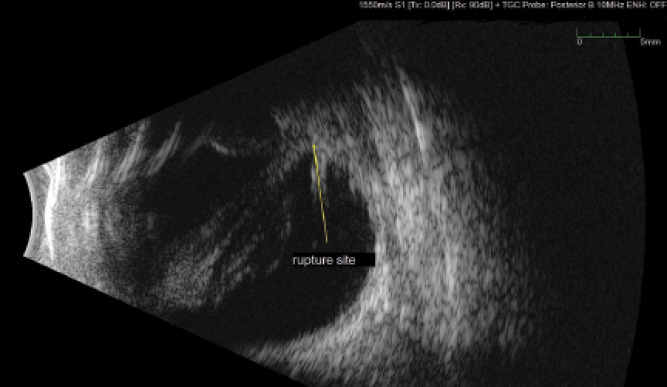

Vitreoretinal traction that cannot be assessed during clinical examination can be evaluated by B-scan ultrasonography in order to plan where to enter the eye to segment the vitreous band causing traction (Figure 6). If the cornea is traumatized but the view is adequate, I proceed with vitrectomy without keratoplasty to release vitreous traction. Wide-angle viewing systems can be used to improve poor visualization.

Figure 6. B-scan ultrasound following a corneal laceration and perforating trauma in a patient’s right eye. Echogenic blood can be seen along the path to the perforation site posteriorly.